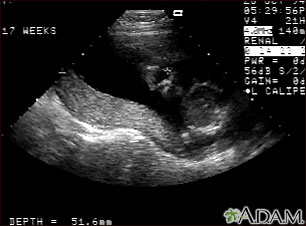

Ultrasonido normal a las 19 semanas de gestación que muestra dos características interesantes. En primer plano, en el centro de la pantalla, se puede observar la placenta siguiendo la curvatura del útero. Al fondo y a la derecha, en el lugar que señala la cruz, se aprecia el rostro con todas las características faciales.